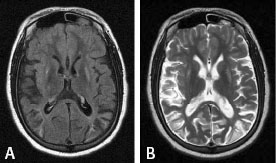

Wilson’s disease showing bilateral

putaminal hyperintensity on T1 and T2,

and multiple cortical ischemic lesions.

Dr. O’Gorman |